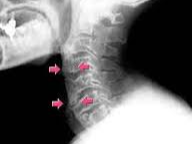

- 영상 검사: 엑스레이나 MRI를 통해 척추와 천장관절의 염증 및 손상을 확인합니다.